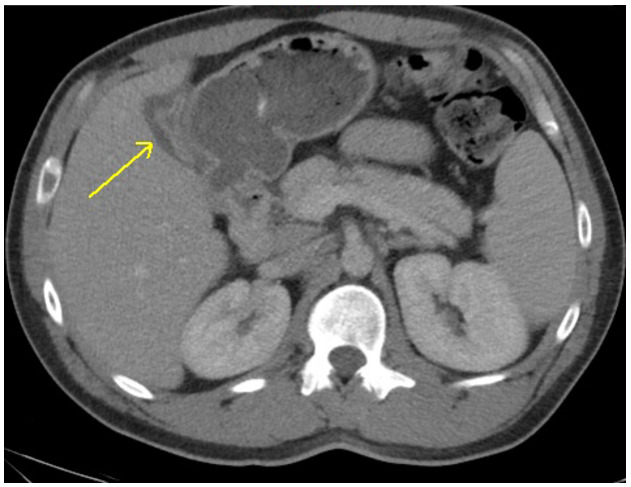

CT of the abdomen and pelvis was interpreted as gall bladder contraction with wall edema and mucosal hyper-enhancement. (Figure 1) No gallstones were identified and the liver, common bile duct and pancreas were all within normal limits. Laboratory evaluation was obtained to evaluate for the degree of liver impairment and was pertinent for thrombocytopenia (88,000), hyperglycemia (451 mg/dL), hyperbilirubinemia (9.2 mg/dL), transaminitis (2238 U/L and 3806 U/L), and elevated PT-INR (i.e., prothrombin time-international normalized ratio) of 15.9 sec/1.54. (Table 1). These laboratory abnormalities suggested possible new-onset Diabetes Mellitus as well as significant liver dysfunction.

Given the radiological findings and suspicion for obstructive jaundice with possible gall bladder infection (i.e., cholecystitis), the authors discussed the case with general surgery. Orders for a magnetic resonance cholangiopancreatography (MRCP) and a viral hepatitis panel were placed for suspected concomitant acute hepatitis. The patient was initiated on IV antibiotics for suspected cholecystitis.